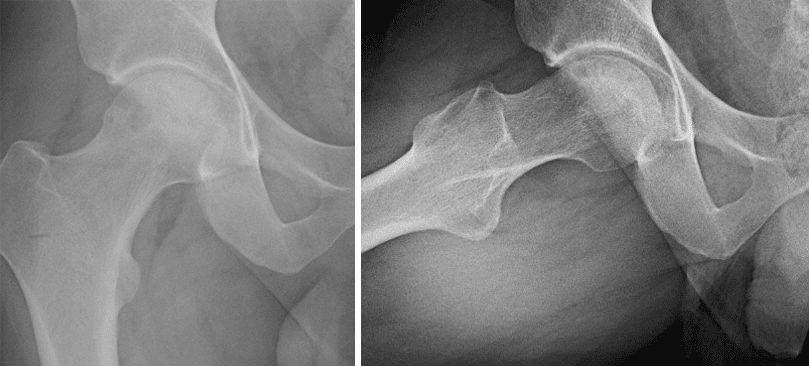

X-rays from two angles showing osteonecrosis of the hip

Two different X-ray views showing osteonecrosis of the hip.

X-rays showing the hip after vascularized fibula grafting for osteonecrosis of the hip

Two X-ray views of the hip after treatment with a vascularized fibular graft.